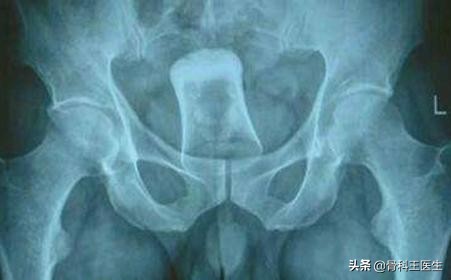

4、肛门、结直肠取异物:

说到从肛门进去,那我们取的东西就太多了,这地方太能装了。